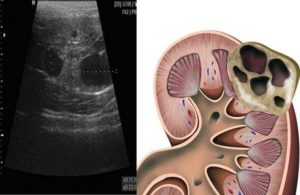

- Ультразвуковое исследование почек, позволяющее определить размеры, расположение и характер содержимого в капсуле новообразования;

- Магнитно – резонансная и компьютерная томографии, использующиеся для составления более полной картины и уточнения результатов, полученных благодаря УЗИ;